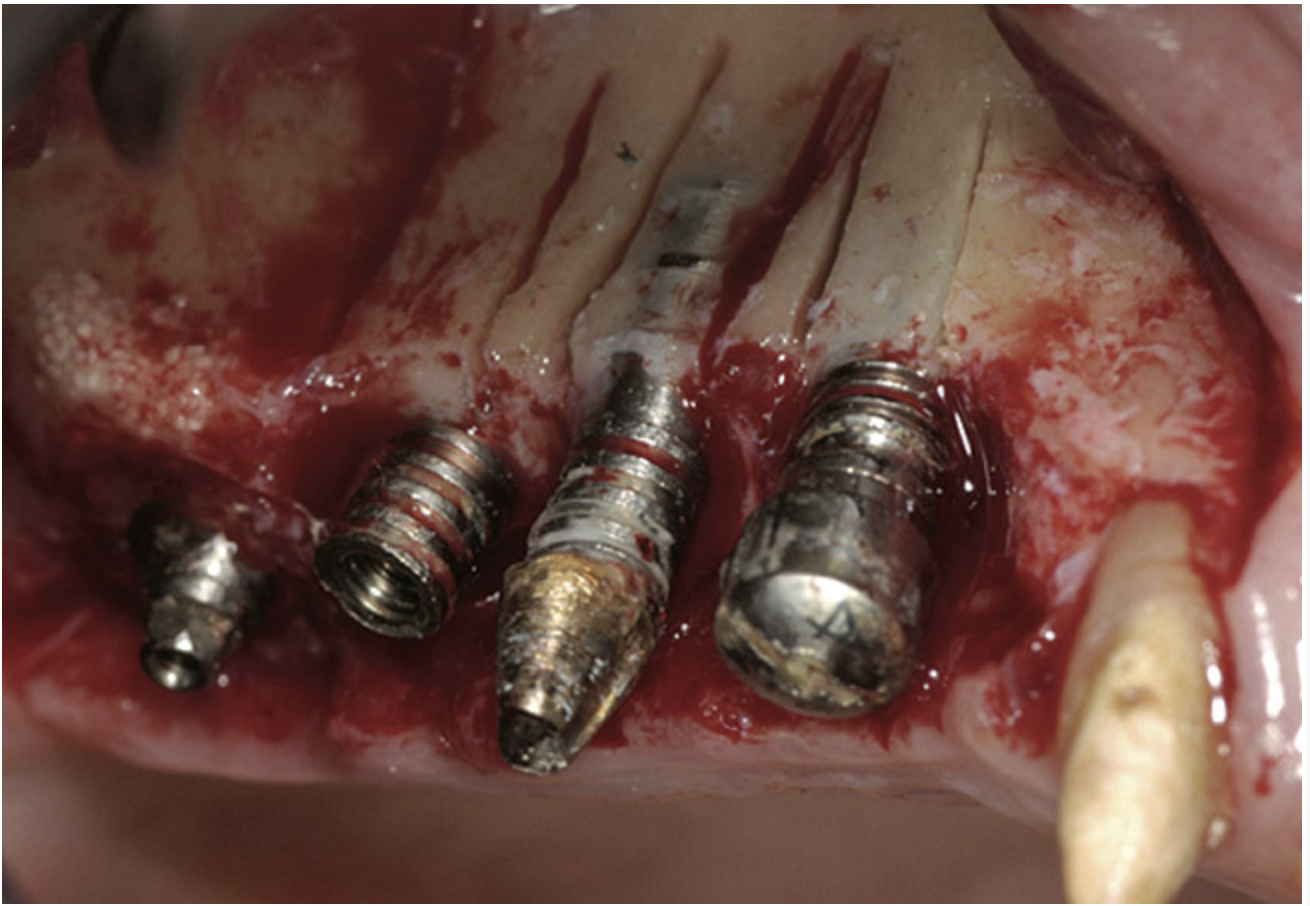

A 72-year-old man was referred for removal of failing maxillary right posterior implants (Figure 19). The treatment plan included removal of three implants with simultaneous bone augmentation and replacement implants for implant-supported fixed bridgework. Implant removal and bone grafting with rhPDGF (Gem 21®, Osteohealth, www.osteohealth.com) and allograft (MinerOss) and xenograft (BioOss®, Geistlick, www.geistlickonline.com) were used along with titanium mesh for space maintenance (Figure 20, Figure 21 and Figure 22). Six months later, mesh removal revealed type I bone allowing for placement of three implants (Figure 23 and Figure 24).

Figure 20  Removal of the failing implants.

Figure 20

Figure 21  Bone grafting with rhPDGF, allograft, and xenograft.

Figure 21

Figure 22  Titanium mesh fixation.

Figure 22